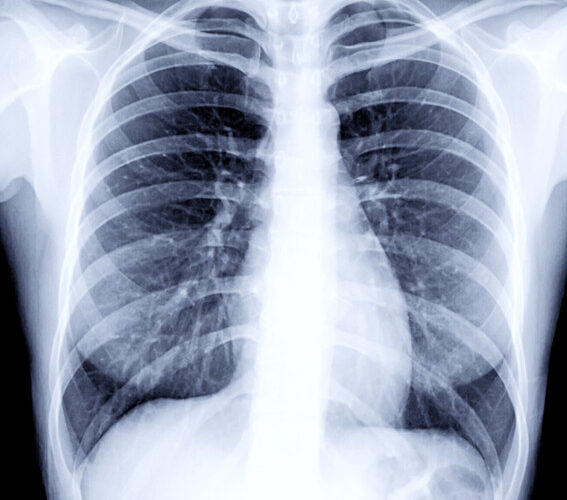

वैदेशिक रोजगारीको लागि अनिवार्य हुने स्वास्थ्य परीक्षणमा Chest X-ray गरिन्छ। यसमा फोक्सो (lungs) को अवस्था हेर्ने गरिन्छ।

छातीमा दाग भन्नाले प्रायः फोक्सोमा पुरानो रोग, संक्रमण वा चोटपटकपछि बाँकी रहेको ‘scar’ (घाउको निशान) लाई जनाउँछ। यो दाग प्रायः सामान्यतया मानिसलाई थाहा नहुने गरी हुन्छ र X-ray गर्दा मात्र देखिन्छ।